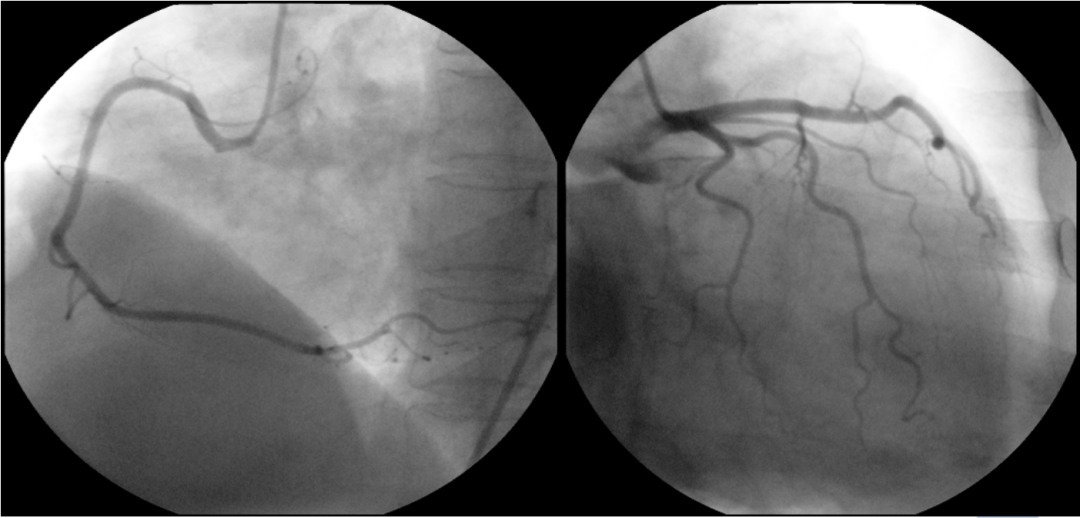

图6 冠状动脉造影